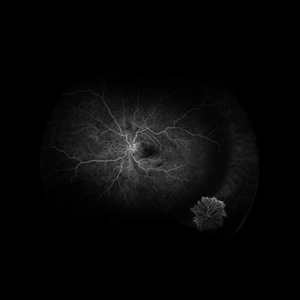

PDR with Peripheral NVEOSFA Early PDR with Peripheral NVEOSFA EarlyJul 23 2024 by Ashley Phillips FA photo of a 62 y/o male with PDR and NVE (periphery) Photographer: Ashley Phillips Imaging device: Optos-California Condition/keywords: PDR with NVE (periphery)